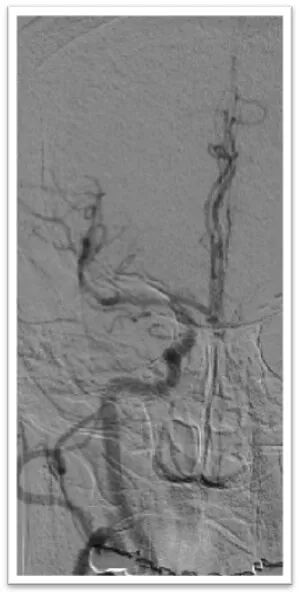

图4:DSA提示主动脉弓为牛角弓,左侧颈总动脉发自头臂干动脉,右侧颈内动脉造影提示前交通动脉开放,呈双干大脑前动脉,左侧大脑前动脉通过软膜支向左侧大脑中动脉供血区域代偿,双侧椎动脉均势供血,左侧大脑后动脉通过软膜支向前代偿供血;左侧颈总动脉闭塞,残端呈杯口状,近端可见白色血栓影,初步考虑栓塞性闭塞。